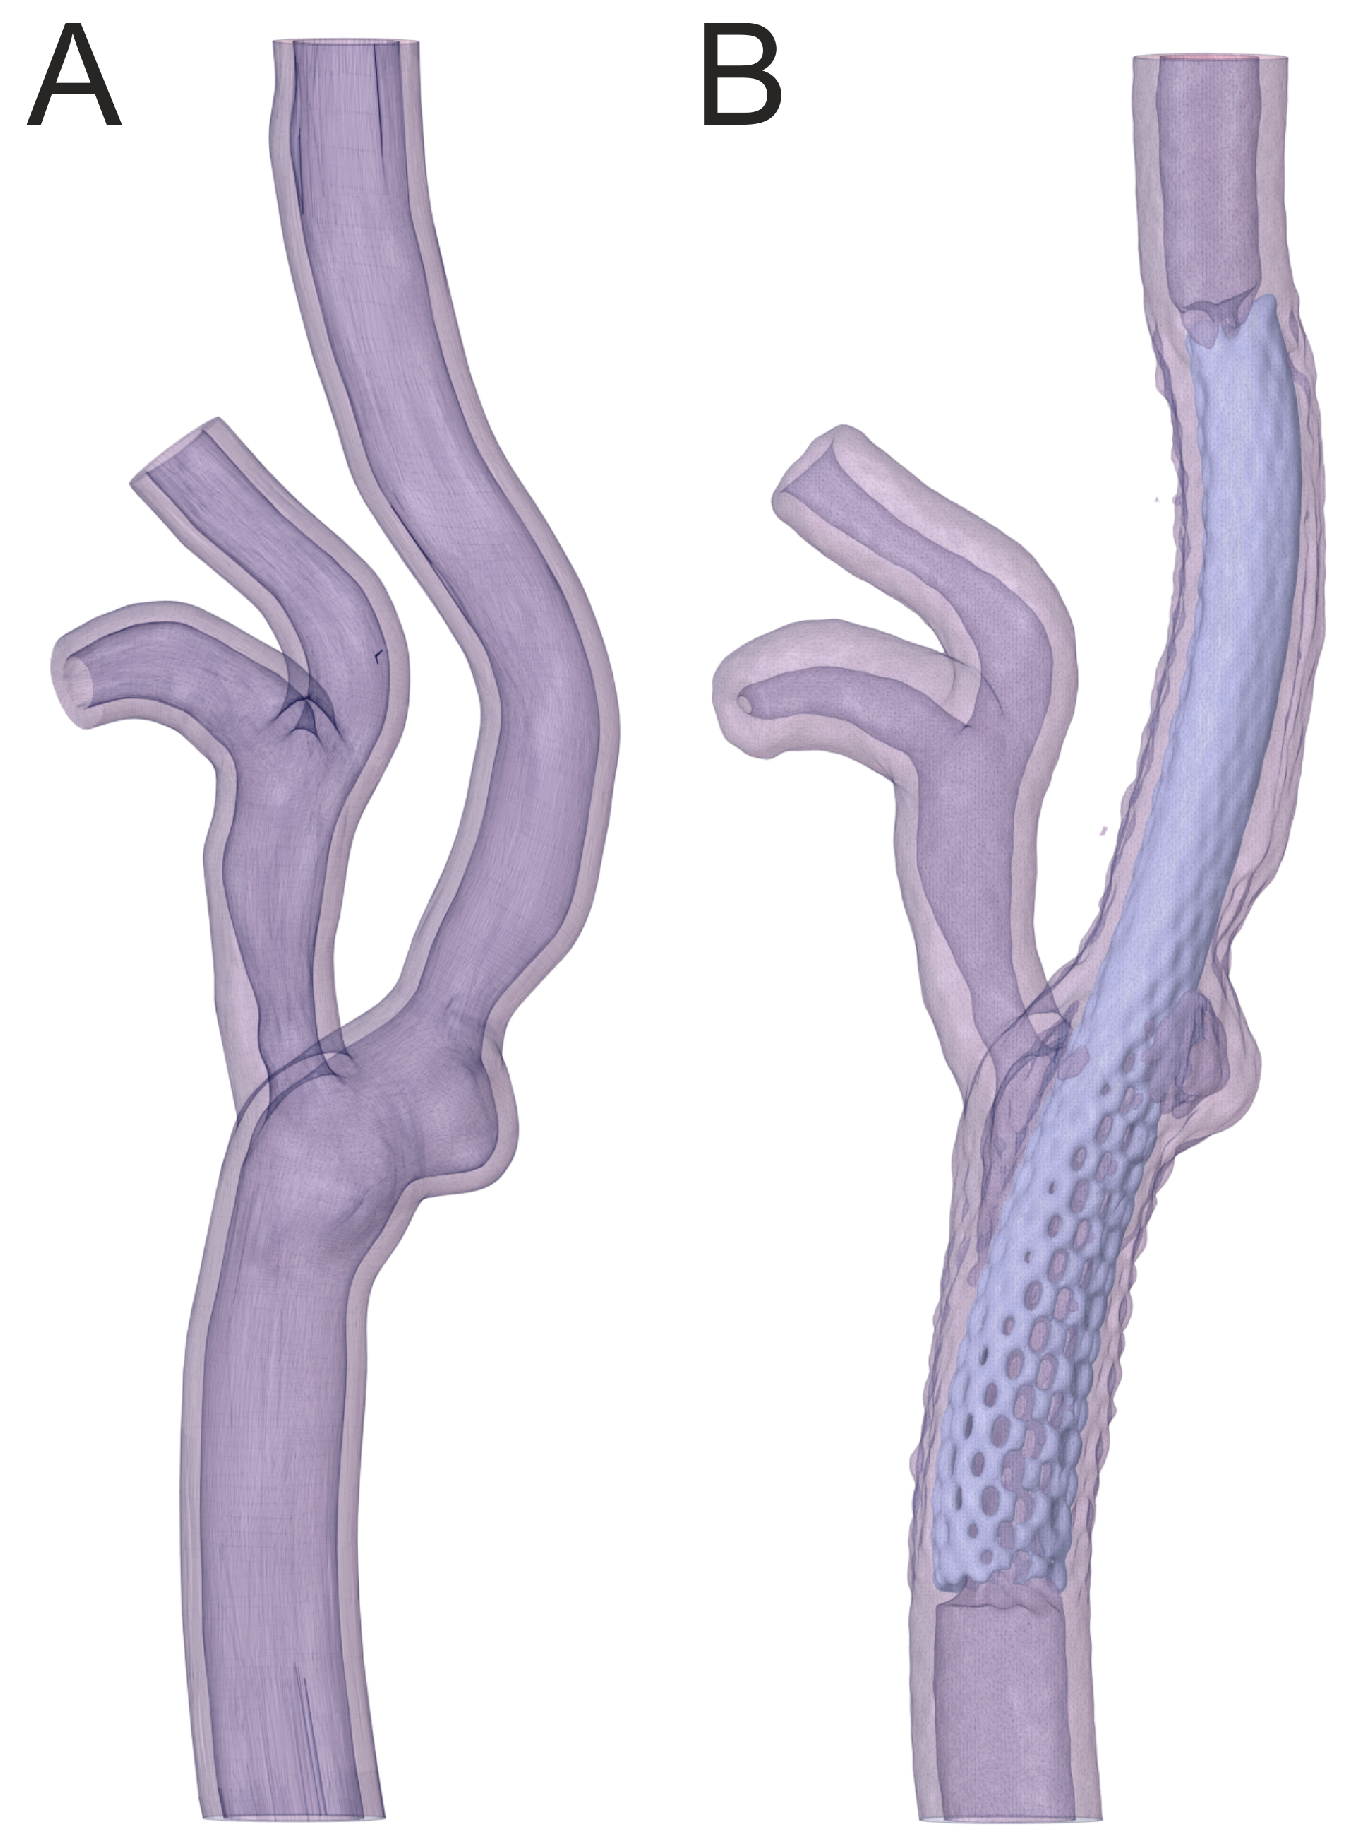

2.1. Geometry Preparation

3.2. Percutaneous Carotid Artery Stenting on 3D-Printed Phantoms